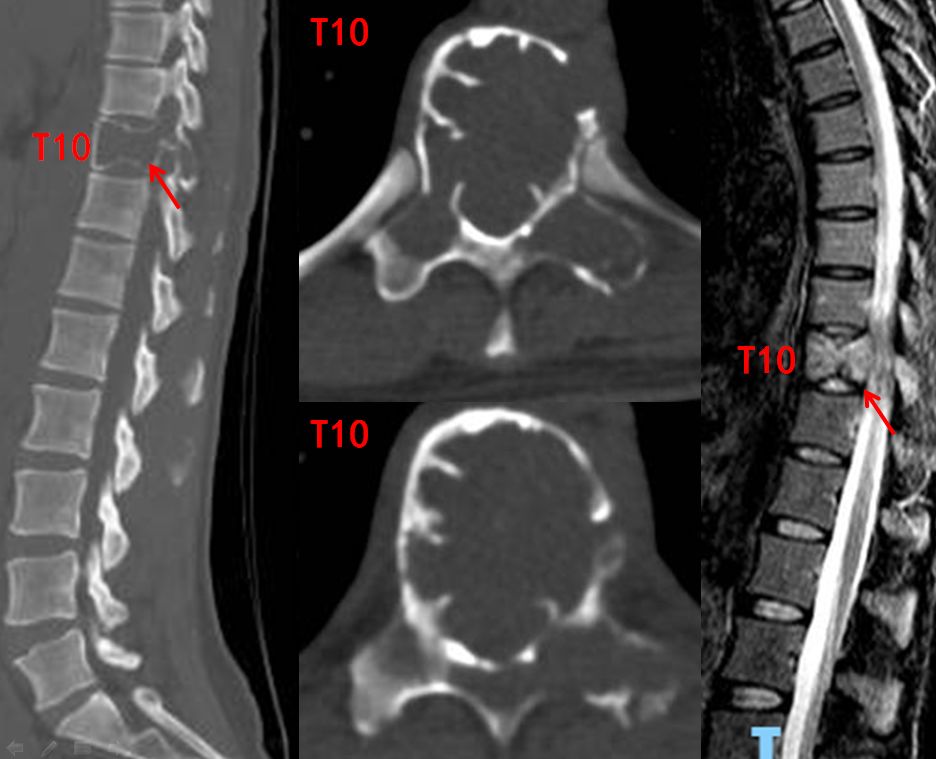

CT及磁共振显示:T10椎体椎体出现骨质破坏及异常信号,整个椎体被肿瘤细胞吃空(箭头处)

胸10椎体穿刺活检显示:骨巨细胞瘤